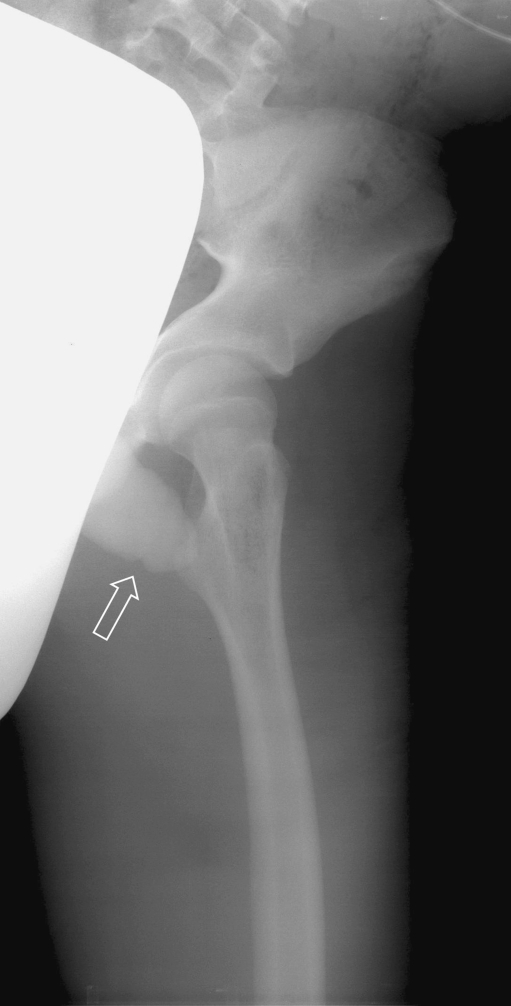

Laboratory values revealed a WBC of 16.7×109/l, platelet count of 12×109/l, BUN of 64 mg/dl, creatinine of 2.4 mg/dl, and a D-Dimer greater than 2,000 ng/ml. CXR showed mild diffuse bilateral pulmonary infiltrates, and the left hip film demonstrated a vague mottled lucency in the intertrochanteric region (Fig. 3). Duplex ultrasound of the left lower extremity was “negative” for deep vein thrombosis (DVT), but soft tissue changes noted around the left common femoral vein were concerning for subcutaneous air. Bedside transthoracic echo was negative for signs of right ventricular strain. Computed tomography of the chest to exclude pulmonary embolism (PE) was deferred in the setting of acute renal insufficiency. ED differential diagnosis included DIC without rash, heparin-induced thrombocytopenia, pneumonic process or PE versus SIRS secondary to an infectious process of uncertain etiology. The patient was aggressively resuscitated with intravenous fluids, prophylactically anticoagulated and initiated on broad spectrum antibiotics after blood cultures were obtained in the ED. The patient was admitted to the pediatric intensive care unit.

Fig. 3.

AP radiograph of the left hip showing a vague, mottled lucency in the intertrochanteric region of the left femur suggestive of intraosseous gas (white arrow); 465×566 mm (96×96 DPI)